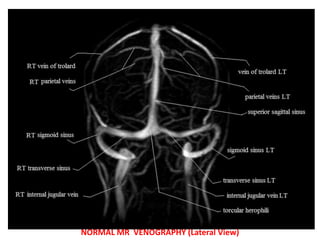

MR VENOGRAPHY

NORMAL MR VENOGRAPHY (Lateral View)

Superior

Sagittal Sinus

Internal

Jugular Vein

Sigmoid Sinus

Transverse Sinus

Confluence

of Sinuses

Straight Sinus

Vein of Galen

Cerebral Vein

NORMAL MR VENOGRAPHY(Lateral View) Superior Sagittal Sinus Internal Jugular Vein Sigmoid Sinus Transverse Sinus Confluence of Sinuses Straight Sinus Vein of Galen Internal Cerebral Vein

NORMAL MR VENOGRAPHY(Lateral View)